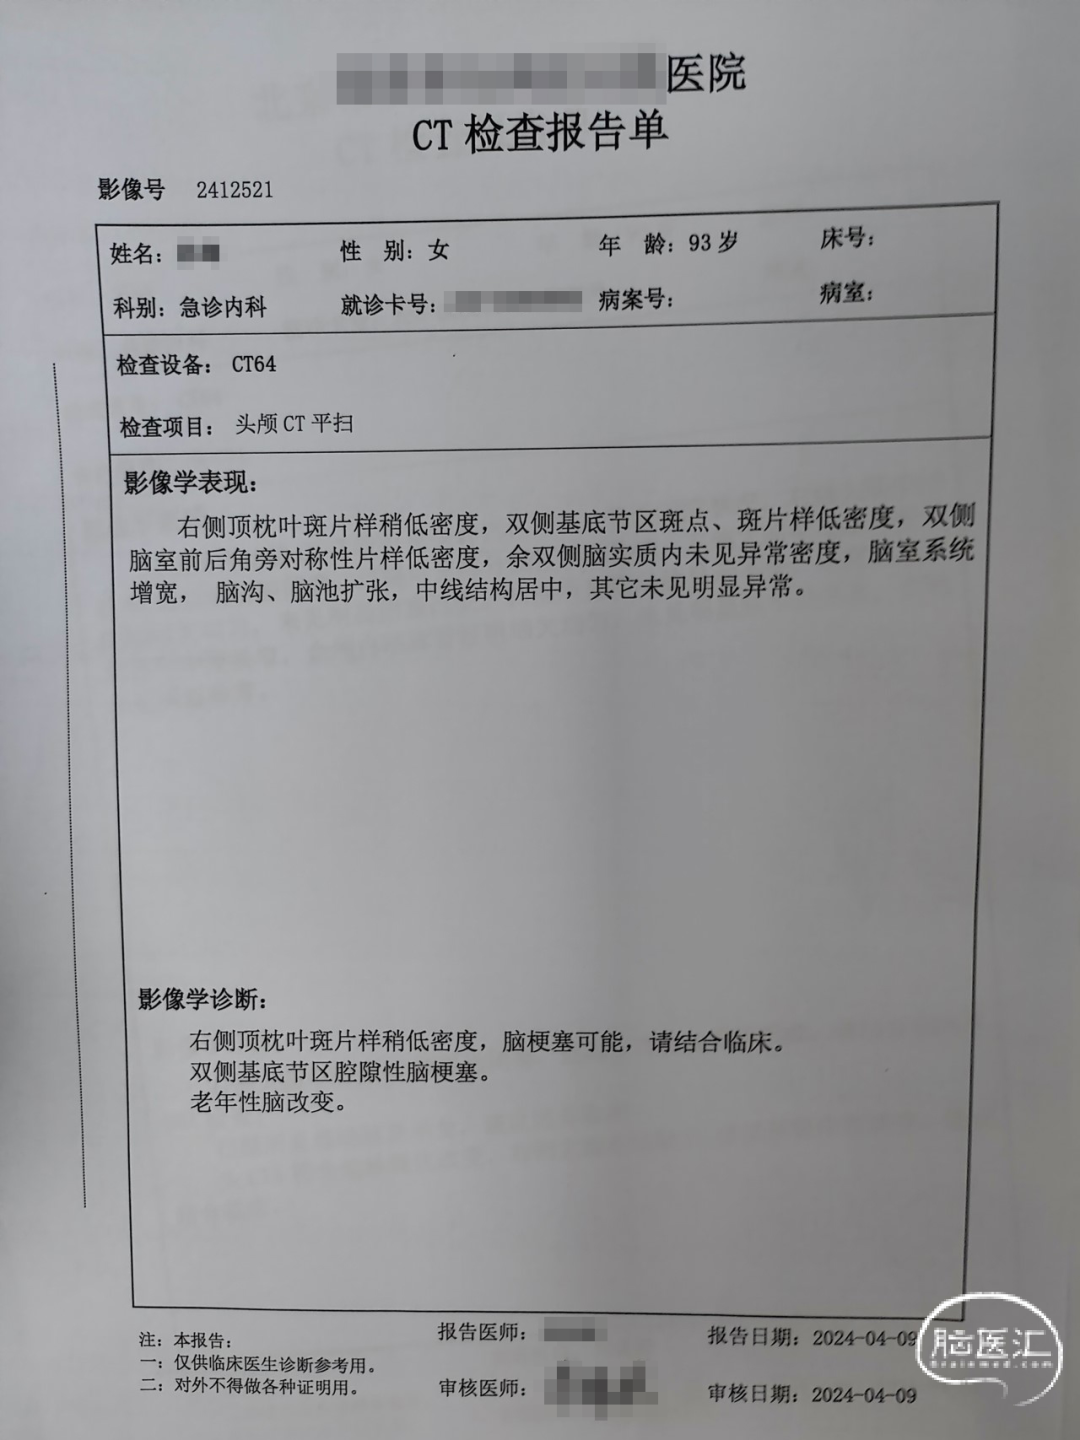

患者:女性,93岁。

主诉:“左侧肢体力弱16小时”于2024.4.9经急诊以“脑梗死”为进一步诊治收入NICU。

现病史:患者2024年4月8日20点左右入睡,4月9日晨起发现患者左侧肢体力弱,完全不能活动,伴双眼向右侧凝视,伴思睡、言语不清,就诊外院,完善头CT:右侧顶枕叶斑片状稍低密度,脑梗塞可能;头CTA:右侧大脑中动脉M2段以远闭塞,远端少许侧支循环形成;头CTP:右侧颞叶、枕叶灌注异常,考虑右侧大脑中动脉闭塞伴部分侧支循环形成。建议患者行脑血管造影、动脉取栓治疗。2.5小时(11:14)前转至我院急诊,收入NICU。

既往史:结肠占位性病变,19天前(2024.3.19)在我院外科行腹腔镜下右半结肠切除术。

入院查体:

血压:BP 165/96mmHg,HR 105次/分,R 15次/分,SPO2 97%。

查体:嗜睡,呼之可应,构音障碍,查体部分合作。双侧瞳孔直径3mm,光反阳性。双侧眼球向右侧凝视。左侧鼻唇沟浅,左侧示齿无力。左侧上下肢肌力0级,右侧上下肢肌力4级。左侧Babinski、Chaddock征阳性。

NIHSS评分18分 (1a+1、1b+2、1c+2、凝视+1、面瘫+2,构音+2、左上+3、左下+3、右上+1、右下+1 )。

头CT(2024.4.9,外院):右侧顶枕叶斑片状稍低密度,脑梗塞可能,请结合临床;双侧基底节区腔隙性脑梗塞;老年性脑改变。

头CTA(2024.4.9,外院):右侧大脑中动脉M2段以远闭塞,远端少许侧支循环形成,请结合临床及DSA检查;符合动脉硬化改变,右侧大脑后动脉P1段局部轻中度狭窄。

头CTP(2024.4.9,外院):右侧颞叶、枕叶灌注异常,考虑右侧大脑中动脉闭塞伴部分侧支循环形成。

血常规(2024.4.9):白细胞:8.15*109/L,中性粒细胞:79.7%,血红蛋白:106g/L,血小板:274*109/L。

血生化:ALT:13U/L,AST:15U/L,白蛋白:39.9g/L,BUN:4.19mmol/L,Cr:54mmol/L,GLU:5.37mmol/L,CK:<25U/L,K+:3.02mmol/L,Na+:140mmol/L,Cl-:101mmol/L。

凝血功能:PT:11.9秒,PT%:88%,INR:1.08,FIB:3.10g/L,APTT:28.4秒,TT:13.5秒。

入院诊断:脑梗死;大脑中动脉闭塞 (右) ;阵发性心房颤动;结肠术后,结肠恶性肿瘤;高脂血症;窦性心动过速;轻度贫血;低钾血症;凝血功能异常;低蛋白血症;反流性食管炎;慢性支气管炎;胸腔积液 (双) ;肺诊断性影像异常。